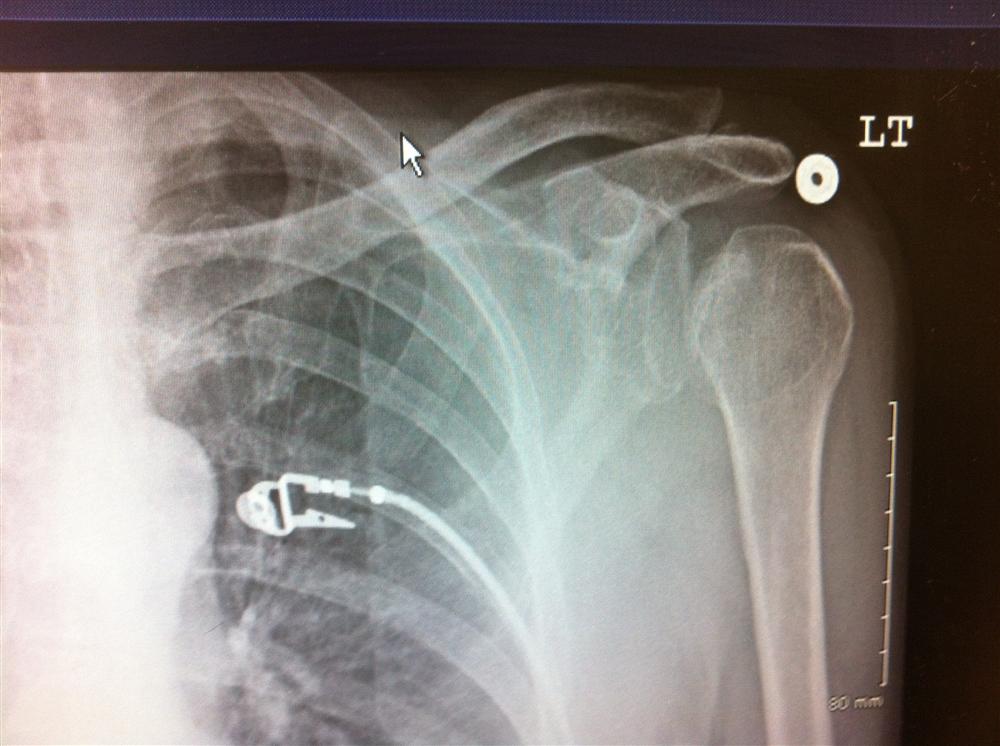

Shoulder Dislocation X Ray Orthobullets . Traumatic anterior shoulder instability, also referred to as tubs (traumatic unilateral dislocations with a bankart lesion requiring surgery), are traumatic shoulder injuries that generally. Provides better detail of cortical and trabecular bone structures than mri at cost of higher radiation exposure. The humeral head will lie medial and inferior to the glenoid fossa. Posterior shoulder instability and dislocations are less common than anterior shoulder instability and dislocations, but are much more commonly missed.

Traumatic anterior shoulder instability, also referred to as tubs (traumatic unilateral dislocations with a bankart lesion requiring surgery), are traumatic shoulder injuries that generally. The humeral head will lie medial and inferior to the glenoid fossa. Posterior shoulder instability and dislocations are less common than anterior shoulder instability and dislocations, but are much more commonly missed. Provides better detail of cortical and trabecular bone structures than mri at cost of higher radiation exposure.